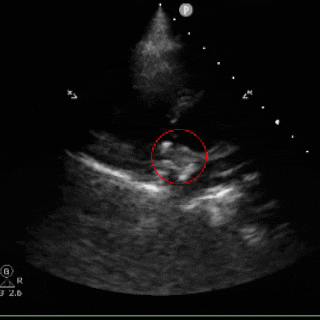

术后心超随访:心脏各房室结构及室壁厚度正常,室壁运动协调,升主动脉及肺动脉内径无异常;房间隔封堵器位置稳定,CDFI证实心房水平未见残余分流。各瓣膜形态及启闭功能正常,未探及明显反流。

超声所见:

各房室腔内径正常范围:房间隔可见封堵器强回声,位置固定;室间隔与左室后壁不厚,呈逆向运动,运动幅度正常;升主动脉内径正常,主肺动脉内径不宽。各瓣膜形态回声正常;

CDFI:房水平未见明显分流信号。心尖四腔心切面流入道呈红色血流束,流出道呈蓝色血流束;频诺多普勒显示,各瓣口均呈层流频谱。

心包腔内未见明显游离液性暗区。

超声提示:

卵圆孔未闭封堵术后

目前心内结构及功能未见明显异常